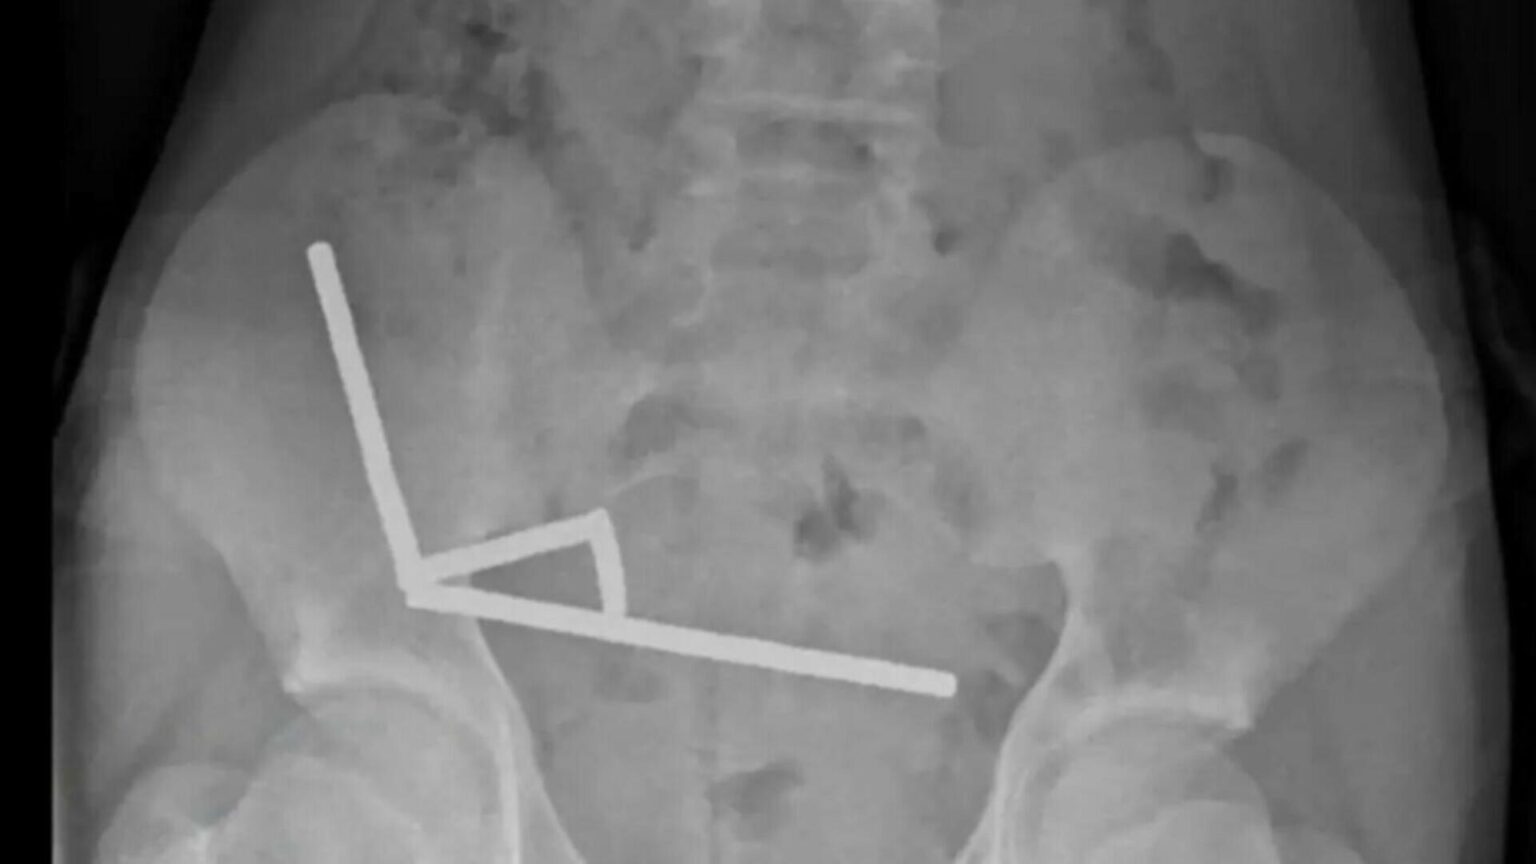

Băiatul a fost internat la Spitalul Tauranga, pe Insula de Nord, după ce a acuzat dureri abdominale intense timp de patru zile. La consultație, a declarat că înghițise între 80 și 100 de magneți mici, dar intervenția chirurgicală a relevat o situație mult mai gravă: în intestinul său se aflau aproape 200 de magneți. Imaginile radiologice au arătat patru lanțuri magnetice prinse în diferite zone ale intestinului, provocând blocarea circulației sângelui și necroză intestinală, o complicație care i-a pus viața în pericol. Medicii au fost nevoiți să îndepărteze o porțiune din intestin pentru a salva pacientul.